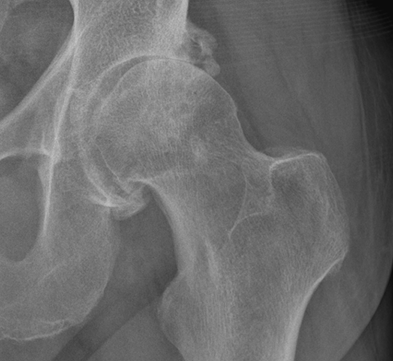

Der Gelenkknorpel sorgt für die reibungslose und schmerzfreie Bewegung der Knochen im Gelenk und schützt die darunter liegenden Knochen vor übermässiger Kraft- oder Druckeinwirkung. Bei einer Hüftarthrose ist dieser schützende Knorpelüberzug abgenutzt, wodurch die Druckbelastung der Knochen steigt und oft Schmerzen entstehen. In der Folge verlieren die Gelenkpfanne und der Hüftkopf ihre Ursprungsformen und bilden Knochenanbauten (Osteophyten). Zudem entstehen Abriebteilchen, die Entzündungen und Schmerzen verursachen. Schätzungsweise 5 bis 10 % der Erwachsenen in Europa haben eine Hüftarthrose mit spürbaren Beschwerden.

Bild: Universitätsklinik Balgrist

Die klinische Verdachtsdiagnose wird durch ein Röntgenbild bestätigt. Andere bildgebende Verfahren wie die Computertomographie (CT) oder die Magnetresonanztomographie (MRT bzw. engl. MRI für magnetic resonance imaging) sind in der Routineuntersuchung oder zur weiteren Abklärung bei primärer Hüftarthrose nicht notwendig. Bei speziellen Fragestellungen sind solche Schnittbildverfahren aber durchaus sinnvoll. Liegen gleichzeitig auch Wirbelsäulen- oder Knieerkrankungen vor, ist eine interdisziplinäre und ganzheitliche Abklärung wichtig.

Die Hüftarthrose wird in 4 Stadien je nach Schweregrad eingeteilt.